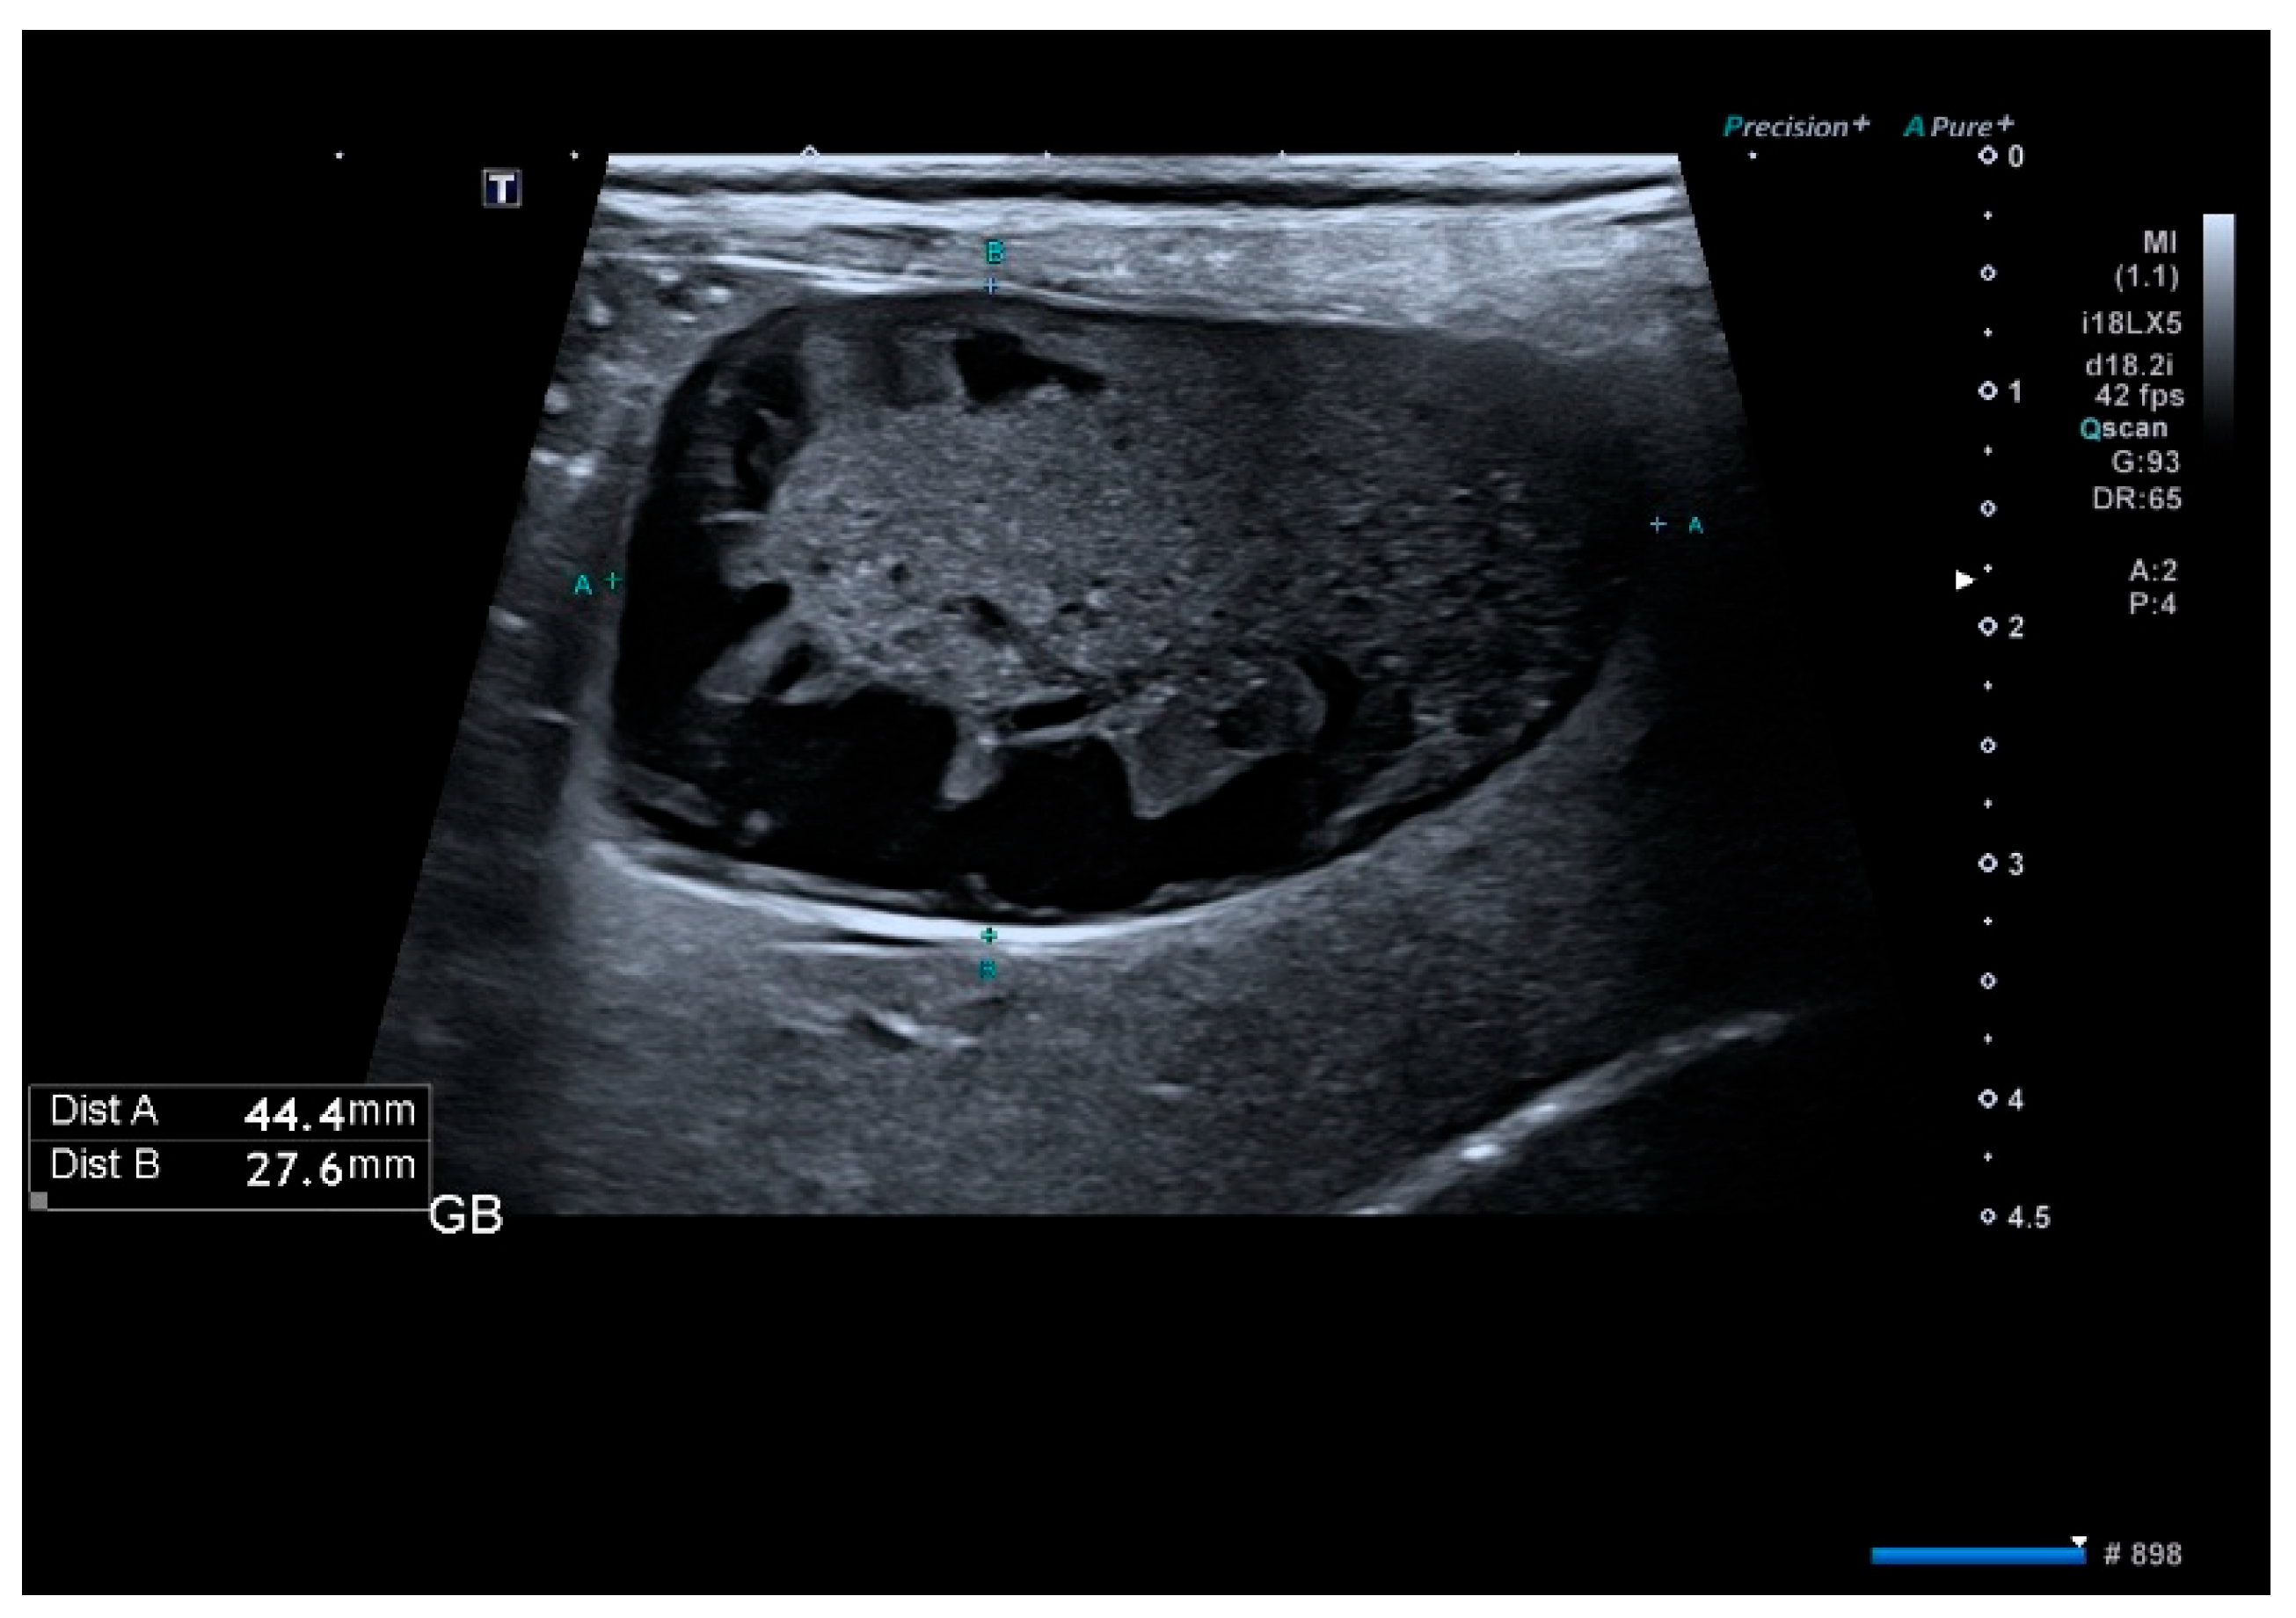

2.3. Imaging Evaluation

3.3. Ultrasound Findings